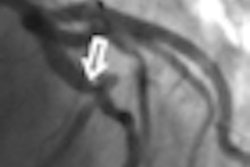

Quebec radiologists have been billing the provincial health insurance agency for analyzing coronary angiograms -- sometimes years after the procedures were carried out -- at a cost of $3 million Canadian per year ($2.4 million U.S.), according to a report by CBC News.

Radiologist interpretation of angiograms is no longer necessary due to technological advances such as digital imaging and real-time results, CBC said. But Radio-Canada's "Enquête" found that some radiologists in Quebec have been filing reports on coronary angiograms months and even years they've been performed, then billing for each one, according to the report.

"Enquête" inspected data from the Centre Hospitalier Universitaire de Sherbrooke (CHUS), choosing at random 200 coronary angiograms performed between 2014 and 2016. It discovered that CHUS radiologists had filed reports on these studies 110 to 879 days after the procedures were completed.

Why would radiologists analyze coronary angiograms after the fact? Sometimes errors can be caught later, stated Dr. Vincent Olivia, president of the Quebec Radiologists Association, in the CBC report. But a delay of this magnitude is not helpful at least and unethical at most, CBC said.